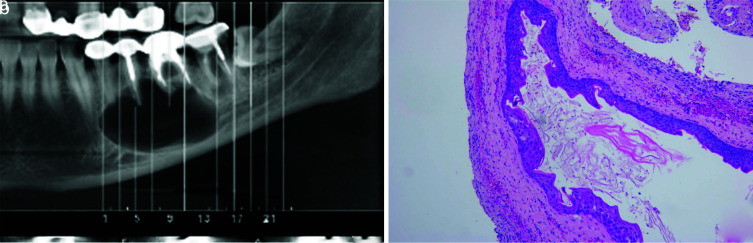

Results:  In the present study, 474 cases were diagnosed with a periapical cyst/granuloma clinico-radiographically, of which 61 cases (12.86%) received a microscopic diagnosis of a non-endodontic pathology. The most frequent lesion was odontogenic keratocyst (n= 12, 19.67%) followed by infected odontogenic cyst (n= 12, 19.67%). About 21.31% of diagnoses were non-cystic lesions and 4.9% were malignancies. The most odontogenic tumors that were diagnosed as periapical cyst/granuloma in clinico-radiography were the ameloblastoma variants (n= 4, 6.55%).

Conclusion:  A wide variety of microscopic diagnoses, including aggressive lesions such as ameloblastoma, as well as other malignant lesions was noted in this study. These misdiagnoses can lead to an inappropriate treatment plan. It is important to microscopically examine all lesions removed from the jaw.

Abstract Image